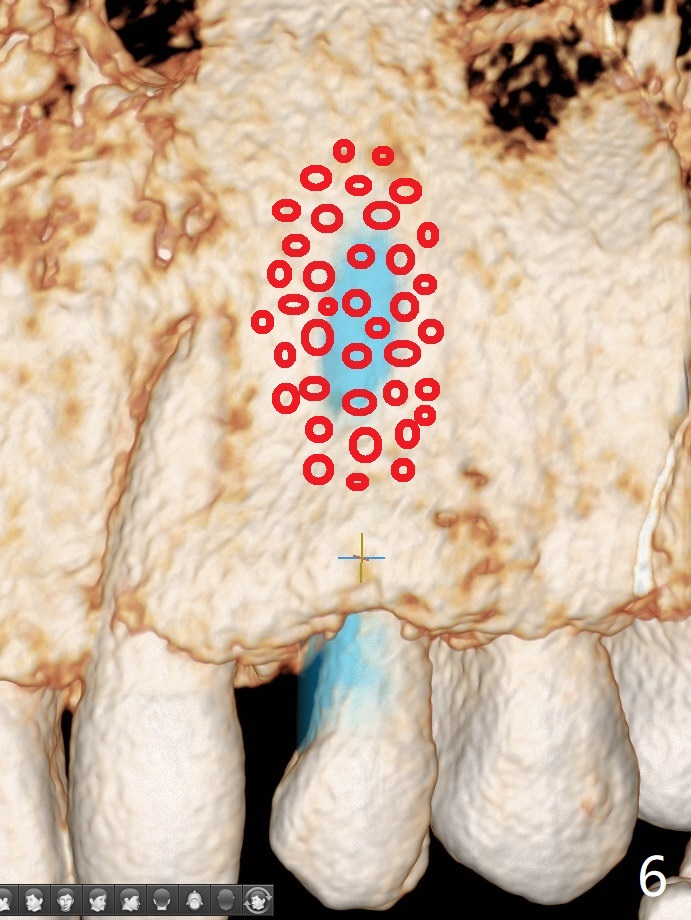

Since there is limited vertical and horizontal (buccopalatal) space at H, it appears that 1-piece implant may offer simple treatment to avoid angled abutment (Fig.1). Because of the thin concave buccal plate over the narrow implant (Fig.2,3,4 *), a remote incision will be made immediately post implantation (Fig.5 red line). After subperiosteal dissection, bone graft will be deposited to avoid implant thread exposure and restore the canine prominence (Fig.6,7). Prepare PRF for sticky bone. Take preop photo to show buccal apical concavity.